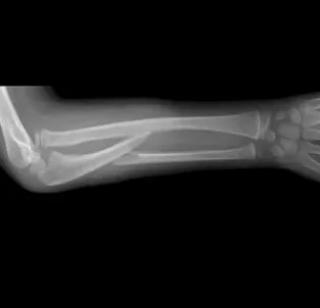

Рентгенологическая диагностика вывиха плеча применяется для подтверждения смещения головки плечевой кости относительно суставной впадины лопатки, выявления сопутствующих костных повреждений и определения направления вывиха. Исследование проводится в прямой (переднезадней), аксиальной и боковой (по Скапула-Й) проекциях. При необходимости выполняются снимки в положении с наружной и внутренней ротацией плеча. Рентгенография является основным методом подтверждения диагноза при травмах плечевого сустава.

Определяется смещение головки плечевой кости вперёд (передний вывих) или назад (задний вывих) по отношению к суставной впадине лопатки.

При переднем вывихе головка локализуется медиальнее и ниже уровня акромиального отростка.

При заднем вывихе выявляется медиальное смещение с внутренней ротацией и уменьшением расстояния между головкой и гленоидом.

Могут выявляться сопутствующие переломы — Hill-Sachs (импрессионный дефект заднелатеральной поверхности головки) или Bankart (отрыв переднего края суставной впадины).

Отмечается деформация контура головки плечевой кости и нарушение её конгруэнтности с суставной впадиной.

На аксиальной проекции уточняется степень смещения и характер вывиха.